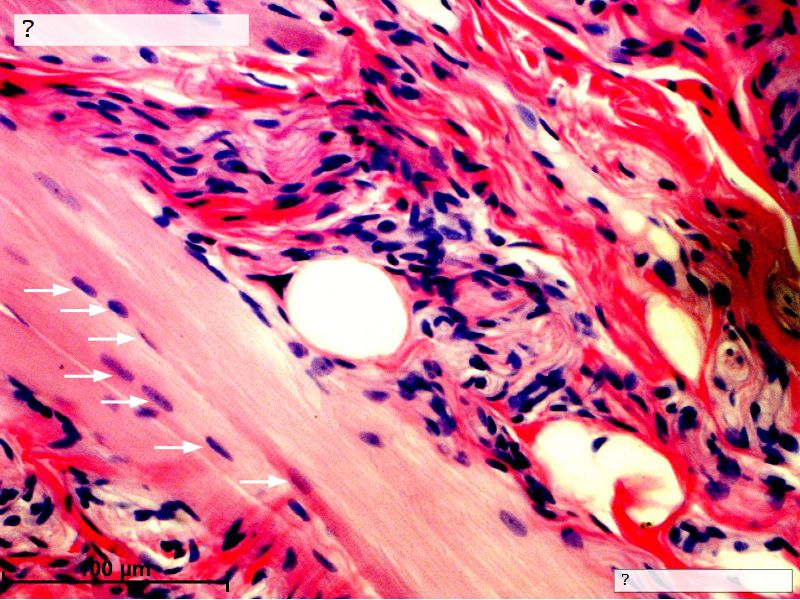

Fill in all the missing labels, and assess as you move through the slides. Answers on the down slide. It is important to do this using pen and paper, and not just glance through the images.